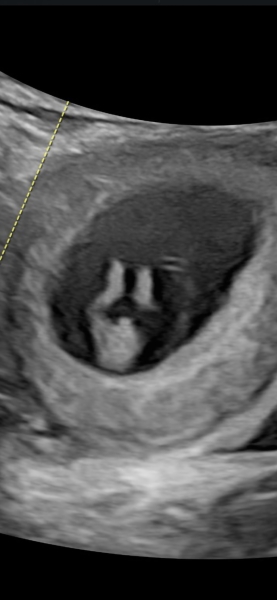

My scan at 13 weeks pregnant. Curious to hear what people think - boy or girl? Appreciate any comments, thankyou! X

Boy :-)